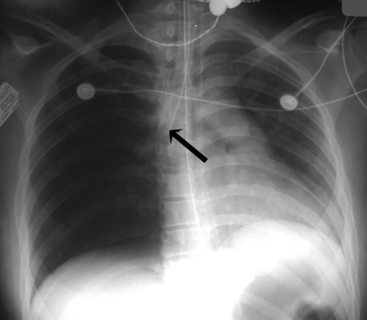

Left atrial enlargement may be difficult to discern on a chest radiograph, because the left atrium normally does not form a distinct portion of the cardiac margin. With left atrial enlargement, the left heart border below the aortic knob may straighten or become convex instead of concave. In addition, the posterior enlargement of this chamber can elevate the left mainstem bronchus so that the angle of the tracheobronchial bifurcation is widened. A double density also may be observed in the center of the cardiac shadow14,21 (Fig. 10-13).

image

Fig. 10-13 Congestive heart failure with pulmonary edema. This 5-year-old boy with known mitral insufficiency was admitted to the critical care unit with tachypnea and increased respiratory effort. On physical examination, he demonstrated a heart rate of 137/min with a gallop rhythm. The respiratory rate was 54/min with moderate retractions. Breath sounds were adequate and equal bilaterally, and crackles were noted, particularly over the left lung fields. The child’s liver was palpable 6   cm below the right costal margin. The child also had cardiomegaly (cardiothoracic ratio of 0.6). The double density seen within the heart (large arrows) is caused by the large left atrium. Pulmonary interstitial markings are prominent and hazy through both lung fields. Kerley B lines are noted in the base of the right lung (small arrows).

(Courtesy Andrew K. Poznanski, Children’s Memorial Hospital, Chicago, IL.)